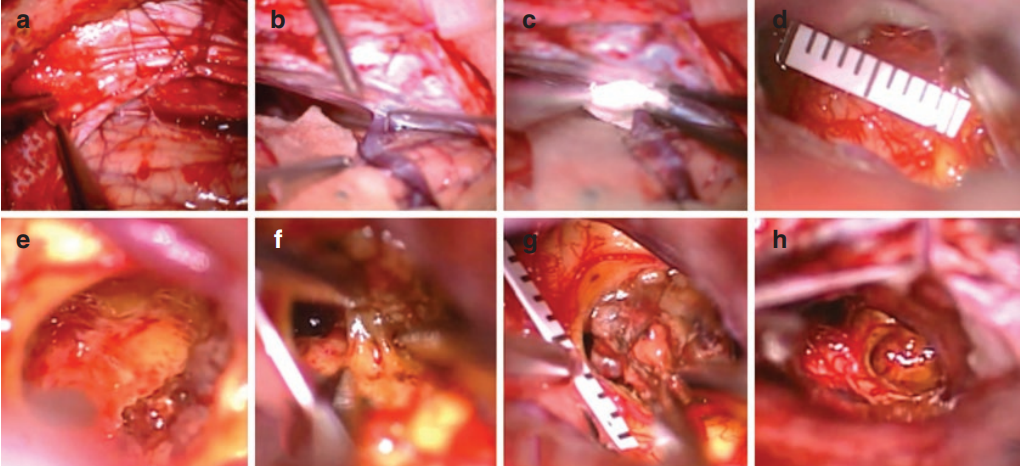

手術(shù)體位及入路:患者被置于半坐位,并計(jì)劃進(jìn)行右側(cè)枕正中/枕下開(kāi)顱(圖2)。

圖2

術(shù)中情況:上顱骨邊緣位于橫竇上方,而硬腦膜在竇下方切開(kāi),然后縫合到該上緣,為此目的放置了鉆孔;鼻竇和天幕被這些帳篷縫合線抬高,而小腦僅靠重力略微下降;無(wú)需使用大腦牽開(kāi)器 (3a)。使用鋒利的鉤子 (3b) 將引流到天幕的小腦四邊形小葉的橋靜脈輕輕地從其周圍的遠(yuǎn)端蛛網(wǎng)膜膜上釋放出來(lái),然后通過(guò)在其進(jìn)入天幕的入口點(diǎn)周圍放置一塊凝膠泡沫來(lái)防止?fàn)恳龘p傷(3C);后者隨后用纖維蛋白膠固定。在初始暴露時(shí),中腦的背側(cè)表面沒(méi)有顯示異常(3d)。進(jìn)入實(shí)質(zhì)的入口點(diǎn)選擇在中腦和丘腦右丘腦之間的過(guò)渡處,因此病變被暴露并從丘腦中分離出來(lái)(3e)。在解剖過(guò)程中,三腦室后部的室管膜壁被打開(kāi)以在三腦室和四疊體池之間建立額外的腦脊液連接 (3f)。表面中腦和丘腦實(shí)質(zhì)的開(kāi)口直徑不超過(guò) 5-6 毫米,小于病變的初始直徑 (3g)。在硬膜內(nèi)階段結(jié)束時(shí)記錄了通過(guò)溫和的雙較電凝和完全切除海綿體畸形進(jìn)行的細(xì)致止血(3h)

圖3:術(shù)中過(guò)程